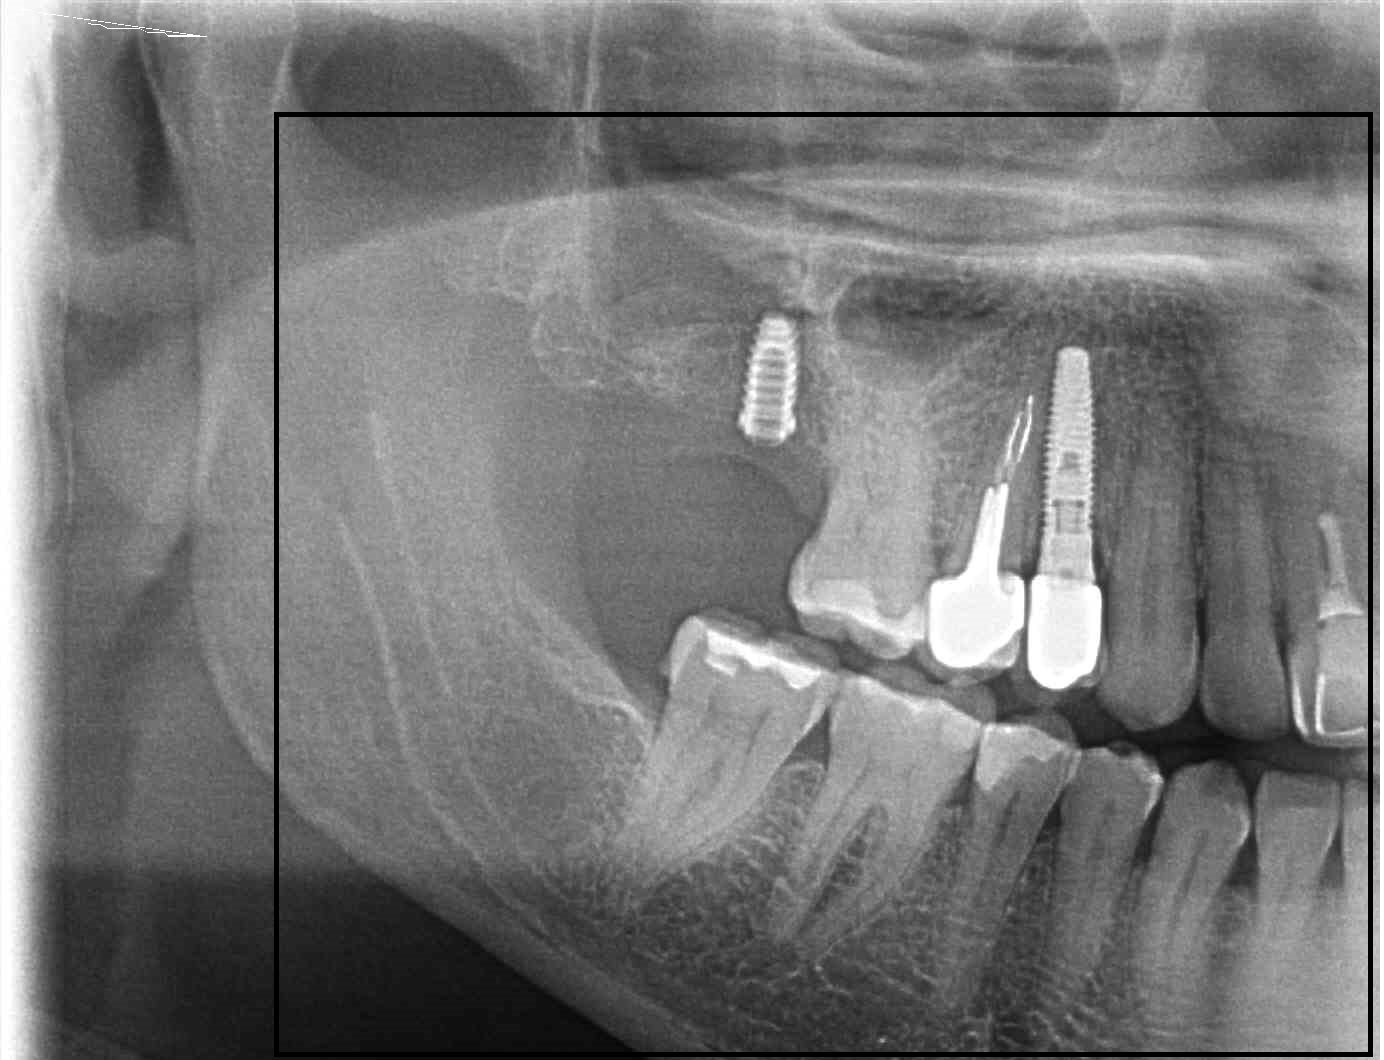

No se que implantes son. Piezas 34,35,44 y45

Buenas tardes. Paciente acude a consulta con implantes colocados en otra clínica en 34,35, 44 y 45. No le llegaron a colocar las coronas. Traspasaron la clínica y al ir [...]